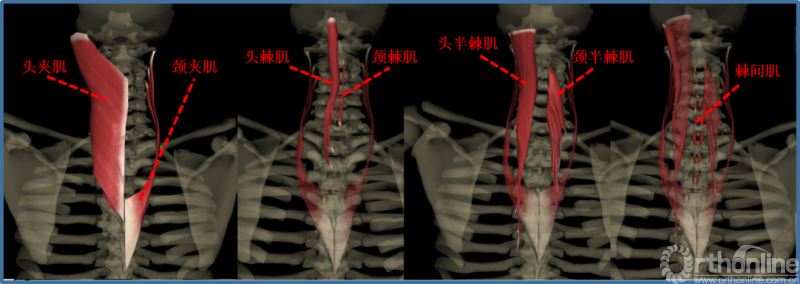

肌肉:

①项背肌分为两层:浅层为斜方肌、菱形肌。深层是颈背部固有肌,长肌在外,短肌在内,共分四层:夹肌、竖脊肌、横突棘肌、枕下肌、横突间肌和棘间肌。

②伸肌装置(中下颈椎)包括斜方肌、夹肌、竖脊肌中的头棘肌和颈棘肌、横突棘肌中颈半棘肌和头半棘肌、棘间肌。附着于棘突及椎板上的颈半棘肌、多裂肌是维持颈椎生理前凸的主要姿势肌群,而以头半棘肌为主的颈伸肌群又是维持颈椎动态稳定的主要因素。

③肌肉韧带复合体:颈半棘肌在颈2棘突下半部宽大的止点+项韧带。是维持颈椎静态和动态稳定的重要结构。

②外侧支发出后则向后走行,多分布于肌肉,支配头长肌、头夹肌、头半棘肌、颈半棘肌及斜方肌等。